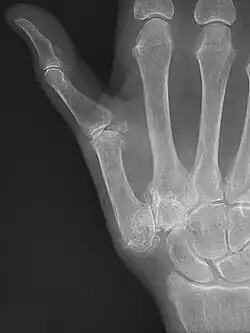

Trapeziometacarpal osteoarthritis (TMC OA) is, also known as osteoarthritis at the base of the thumb, thumb carpometacarpal osteoarthritis, basilar (or basal) joint arthritis, or as rhizarthrosis.[3][1][2] This joint is formed by the trapezium bone of the wrist and the metacarpal bone of the thumb. This is one of the joints where most humans develop osteoarthritis with age.[4] Osteoarthritis is age-related loss of the smooth surface of the bone where it moves against another bone (cartilage of the joint).[3][5] In reaction to the loss of cartilage, the bones thicken at the joint surface, resulting in subchondral sclerosis. Also, bony outgrowths, called osteophytes (also known as "bone spurs"), are formed at the joint margins.[6]

There may be enlargement at the TMC joint.[8] This area may be tender, meaning it is painful when pressed. There may also be hyperextension of the metacarpophalangeal joint. The thumb metacarpal deviates towards the middle of the hand (adduction).[12] Also a grinding sound, known as crepitus, can be heard when the TMC joint is moved, more so when axial pressure is applied.[13]

TMC OA is diagnosed based on symptoms and signs.[8] Radiographs can confirm the diagnosis and the severity of TMC OA. Other diagnoses in this region include scaphotrapezial trapezoid arthritis and first dorsal compartment tendinopathy (De Quervain syndrome) although these are usually easy to distinguish.